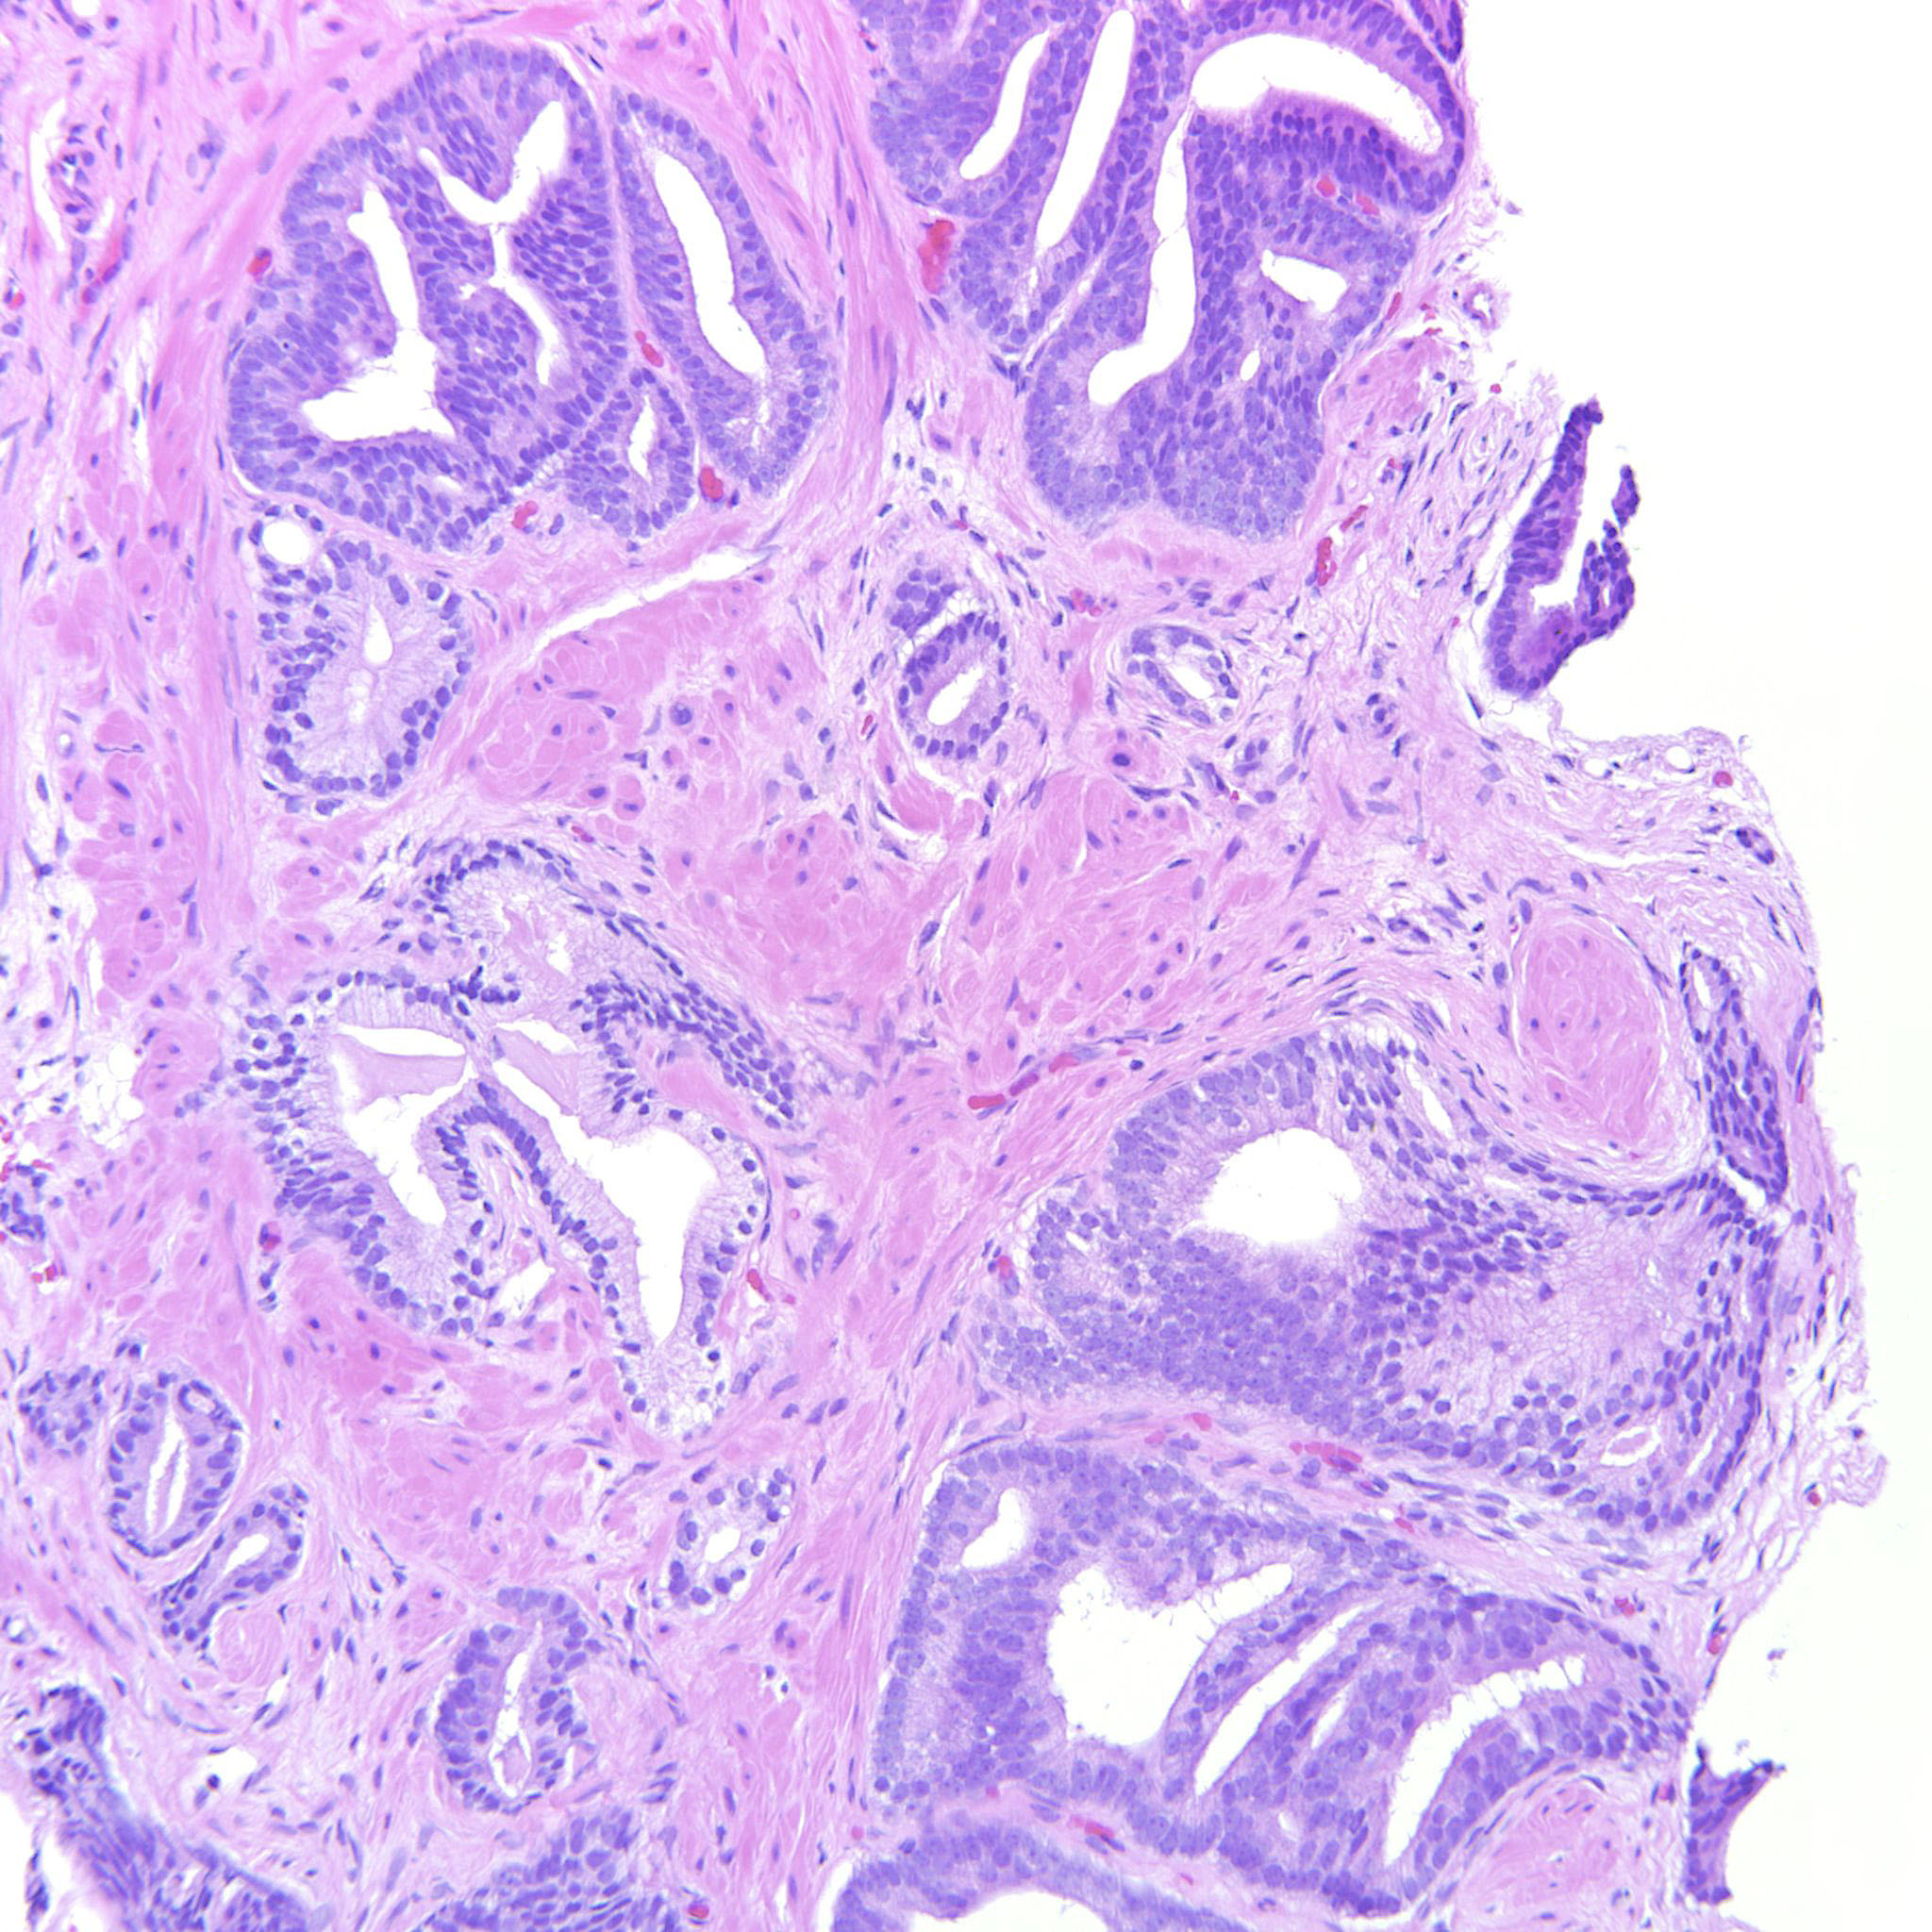

Consensus grade: GS 3+4=7 (ISUP 2)

Case description (by case creator):

A lot of the tumor is GP3 but there are also a couple of cribriform glands. The epithelium is tall columnar, sometimes with elongated nuclei but the tumor does not have other features of ductal adenocarcinoma and should probably be considered a variant of acinar adenocarcinoma of the prostate.